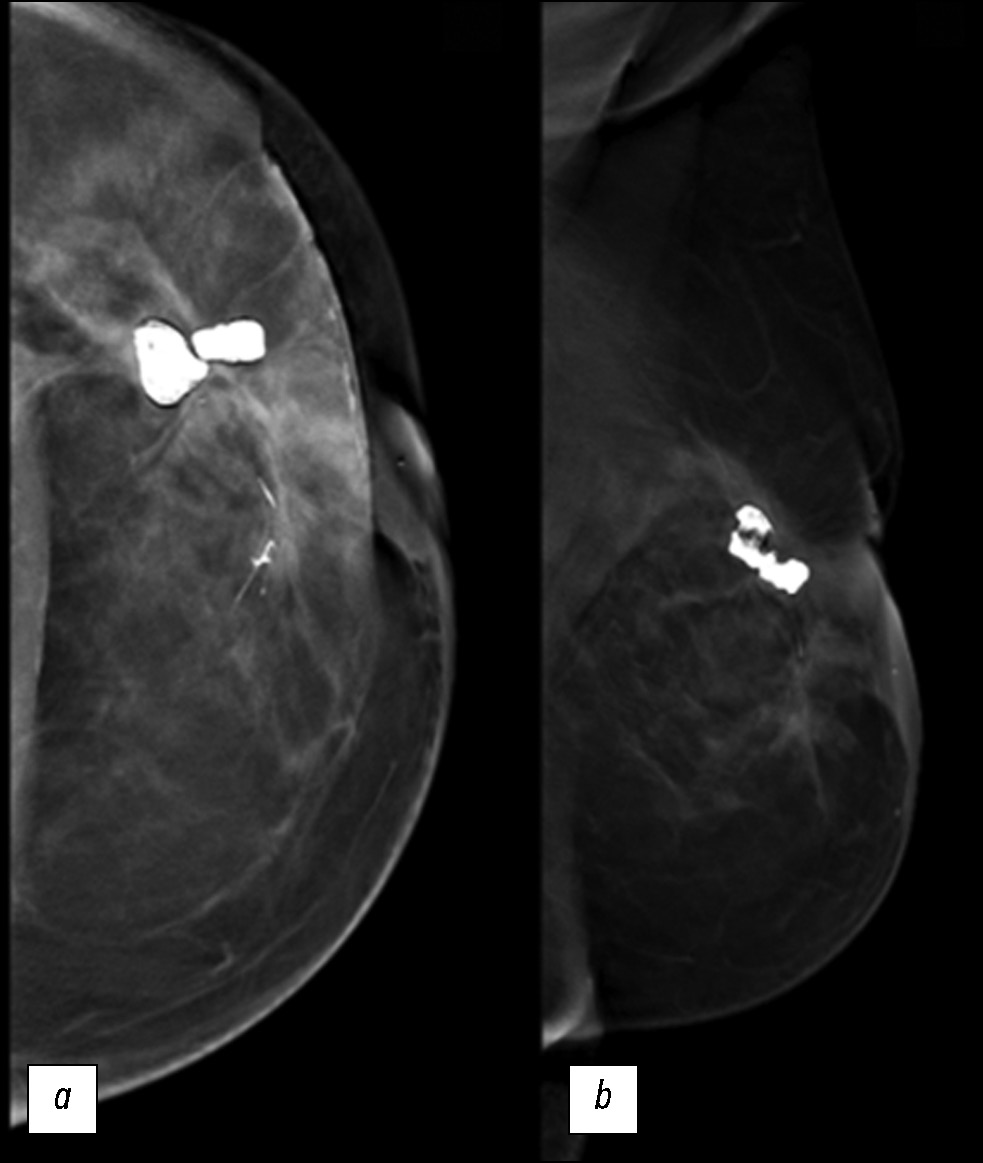

Navigating secondary breast angiosarcoma: a case report

We describe a rare case of secondary breast angiosarcoma in a 72-year-old woman with a history of breast cancer who presented to our clinic with a painless palpable mass in the outer upper quadrant of the left breast. The diagnosis required a multidisciplinary approach involving a senologist, anatomopathologist, and oncologist. Imaging modalities such as mammography, ultrasonography, and magnetic resonance imaging made it possible to assess the extent of the tumor, lymph node involvement, and distant metastases. The diagnosis was confirmed by a tissue biopsy. Herein, a rare case is presented, with the main educational purpose of describing the clinical presentation and complex diagnostic evaluation and discussing the differential diagnosis and management. Indeed, secondary mammary angiosarcoma is a rare and aggressive neoplasm, and understanding its unique features is essential for clinical decision-making and patient outcomes. The tumor has a worse prognosis because of its late diagnosis, higher risk of rapid distant spread, and limited treatment options. Such cases require close monitoring, aggressive strategies, and supportive care.